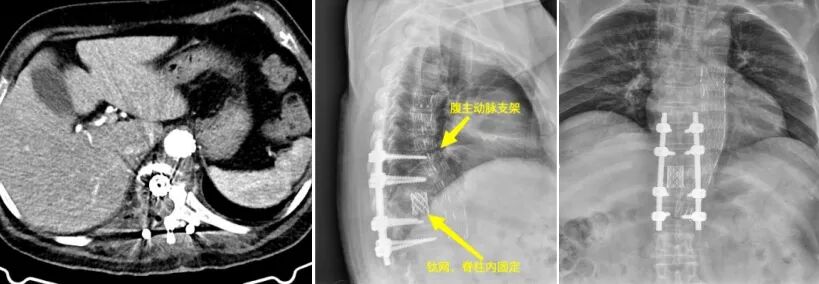

圖1.圖2:術(shù)前見腹主動(dòng)脈瘤與胸9-11椎體病灶緊密相連 圖3.圖4:動(dòng)脈瘤術(shù)前三維影像 面對(duì)這一復(fù)雜病情,貴陽市公共衛(wèi)生救治中心骨外科迅速與貴州醫(yī)科大學(xué)附屬醫(yī)院血管外科進(jìn)行溝通,共同決定采取聯(lián)合手術(shù)治療方案。在兩家單位共同努力下,患者成功進(jìn)行了降主動(dòng)脈-腹主動(dòng)脈覆膜支架腔內(nèi)隔絕術(shù)。手術(shù)后,患者的腹主動(dòng)脈瘤得到了有效控制,血管外科團(tuán)隊(duì)也順利完成了血管修復(fù)工作(圖5-6)。 圖5.圖6:降主動(dòng)脈-腹主動(dòng)脈覆膜支架腔內(nèi)隔絕術(shù)術(shù)后 隨后,貴陽市公共衛(wèi)生救治中心骨外科對(duì)患者實(shí)施了“胸椎結(jié)核病灶清除+椎體次全切除+鈦籠植骨融合+椎弓根螺釘內(nèi)固定術(shù)”(圖7-11)。手術(shù)成功地完成了胸椎結(jié)核病灶的清除,并進(jìn)行了脊柱的重建。目前,患者已經(jīng)能夠下地行走,下肢的感覺也得到了恢復(fù)。 圖7.圖8.圖9:胸椎結(jié)核術(shù)后影像 圖10.圖11:術(shù)后三維影像 “患有腹主動(dòng)脈瘤和胸椎結(jié)核的病人相對(duì)罕見,治療過程復(fù)雜且手術(shù)風(fēng)險(xiǎn)高,需要多學(xué)科的緊密合作。這次病例的成功治療,充分體現(xiàn)了貴陽市公共衛(wèi)生救治中心骨外科與貴州醫(yī)科大學(xué)附屬醫(yī)院血管外科之間的高效醫(yī)療協(xié)作和專業(yè)實(shí)力,同時(shí)也為處理類似復(fù)雜疾病提供了珍貴的臨床經(jīng)驗(yàn)?!辟F陽市公共衛(wèi)生救治中心骨外科脊柱組組長(zhǎng)任鵬醫(yī)師表示,“跨學(xué)科的聯(lián)合治療,能夠很好地應(yīng)對(duì)復(fù)雜病情,提高治療的成功率,切實(shí)為人民群眾提供安全優(yōu)質(zhì)的服務(wù)?!?/p> 貴陽市公共衛(wèi)生救治中心骨外科簡(jiǎn)介 貴陽市公共衛(wèi)生救治中心外一科(骨外科)成立于2009年11月,是省內(nèi)唯一的骨與關(guān)節(jié)結(jié)核??萍案腥竟强?。在過去的十年中,成功治療了約4500例骨結(jié)核患者,診療效果和服務(wù)享有較好口碑。目前,科室已擴(kuò)展為三個(gè)亞??平M:脊柱組、關(guān)節(jié)創(chuàng)傷組和頭頸外科組。開展脊柱、關(guān)節(jié)等骨感染疾病、頸部疾病以及骨折、脊柱關(guān)節(jié)退行性疾病、骨腫瘤手術(shù)等治療。此外,科室還負(fù)責(zé)HIV相關(guān)骨科疾病的診治工作。 患者可根據(jù)個(gè)人需求選擇骨科專家門診或普通門診服務(wù),骨外科提供全天候24小時(shí)的醫(yī)療服務(wù)。目前,科室開展了一系列具有挑戰(zhàn)性的手術(shù)治療,包括復(fù)雜脊柱(頸胸腰)、關(guān)節(jié)結(jié)核手術(shù)、四肢關(guān)節(jié)創(chuàng)傷及椎體成形術(shù)、初次人工全髖關(guān)節(jié)置換術(shù)、初次復(fù)雜及人工髖關(guān)節(jié)翻修術(shù)、初次人工膝關(guān)節(jié)置換術(shù)、復(fù)雜初次及人工膝關(guān)節(jié)翻修術(shù)、嚴(yán)重粉碎性骨盆及髖臼骨折等。此外,科室還涵蓋綜合醫(yī)院骨科大部分常見、多發(fā)疾病的手術(shù)及保守治療??剖遗鋫淞酥行虲臂X光機(jī)、電動(dòng)磨鉆、骨折治療儀、中頻/低頻治療儀、下肢CPM功能鍛煉器、空氣壓力波等多種先進(jìn)設(shè)備。針對(duì)脊柱、關(guān)節(jié)疾病患者的主要臨床癥狀,如頸肩疼痛、腰腿疼痛、四肢關(guān)節(jié)疼痛、下肢活動(dòng)障礙等,科室還開展了中藥穴位貼敷、藥棒穴位按摩、艾灸等特色中醫(yī)治療,以滿足臨床需求,為患者提供高質(zhì)量的服務(wù)。 咨詢電話:0851-85959033